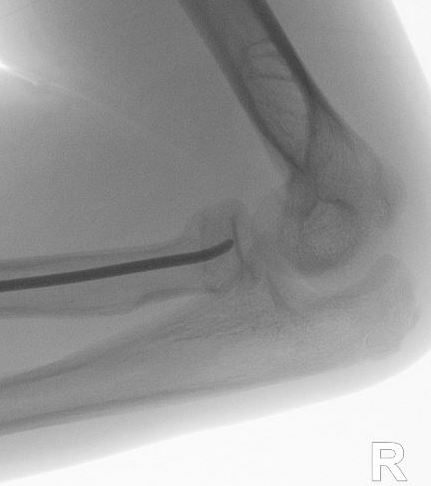

Xray

Displaced and angulated radial neck fracture